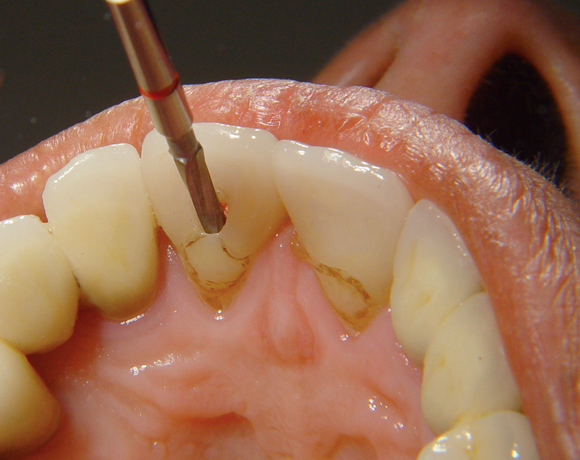

Der Dentinpost Stift ist die Antwort auf den zu harten Cerapost Stift, er ist aus Glasfaser und damit der Härte des Wurzeldentins angepasst.

Bei diesem Patientenfall musste nach Neuüberkronung der Frontzähne eine Wurzelbehandlung erfolgen. Um der Gefahr aus dem Weg zu gehen, dass die neue Krone abbricht, da sehr wenig eigene Zahnrestsubstanz nach der endodontischen Behandlung übriggeblieben war, wurde der Zahn nachträglich mit einem Dentinpost versorgt.